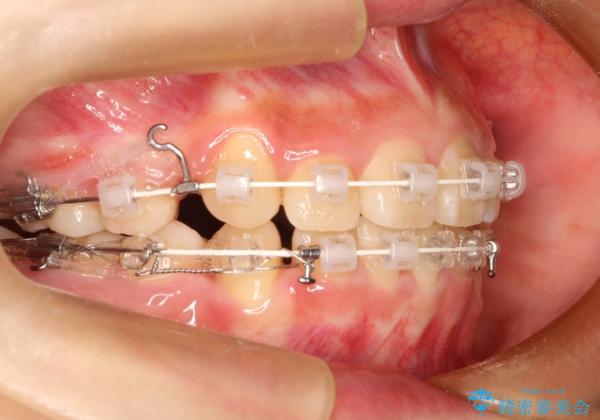

- 矯正装置

- 審美装置

- 上下左右4本の小臼歯を抜歯、ラビアル・ワイヤー矯正を計画した。

抜歯をして第1小臼歯分のスペースを獲得することにより、ガタつきの改善と前歯のリトラクトをおこない、横顔の印象もすっきりとし、整ったEラインを作ることができました。